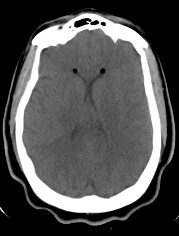

Diagnostic Testing. The patient’s CT brain imaging revealed a small amount of air in both frontal horns of the lateral ventricles (Figure 1). Her brain CTA revealed distension of the superior sagittal sinus (SSS), inferior sagittal sinus, transverse sinus, and vein of Galen and an extra-axial SSS defect (Figures 2-4). The initial report of the MRI brain with and without contrast redemonstrated trace pneumocephalus but was otherwise unremarkable. Later review after 10 days, revealed pachymeningeal enhancement, venous sinus distension, and a filling defect in the SSS suggestive of venous sinus thrombosis (Figures 5, 6). Her MRI of the cervical spine did not reveal another cause of neck pain, and her urine protein was negative.

Fig. 1. Nondependent pneumoventricle within the bilateral frontal horns of the lateral ventricles.